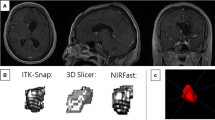

Assessing relative volume differences there are some extreme values, namely 73% (case 20) in segmentation cycles 1 vs. 2 and 55% (case 2) and 45% (case 4) in segmentation cycles 2 vs. 3 (Fig. 2). Case 20 is a left insular glioma considered to have well-defined borders. It was the second tumor segmented in the very beginning, and with more experience the tumor borders were interpreted quite different and more consistently the second and third time, showing a smaller difference of 19%. Case 2 resides in the right insula and case 4 in the left medial temporal lobe. Both were classified to have “absent” tumor borders, making them difficult to delineate consistently. In addition, case 4 is a rather small tumor, with a mean volume of only 2 mL.

Three tumors with extreme differences. Case 20 without (a) and with (b) segmentation label, segmentation 1 outlined in red and segmentation 2 in yellow. Case 2 without (c) and with (d) segmentation label, segmentation 2 outlined in red and segmentation 3 in yellow. Case 4 without (e) and with (f) segmentation label, segmentation 2 outlined in red and segmentation 3 in yellow